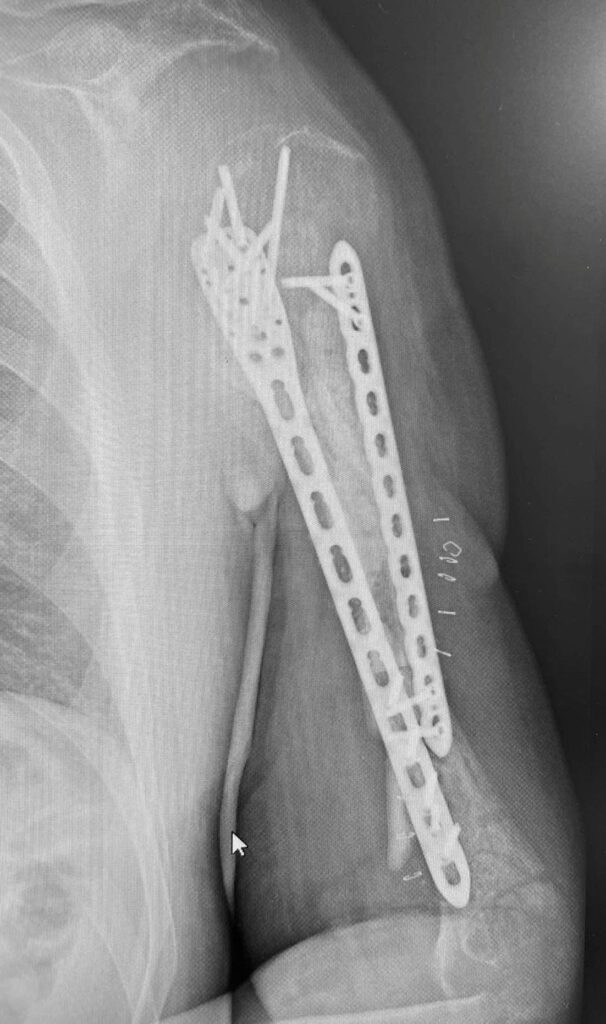

Возможно, что вы помните примерно двухнедельной давности наш с друзьями пост «Ампутировать или сохранять?». Речь шла о буквально разрушенном плече у воина ЗСУ в результате минно-взрывного ранения.

На первых этапах несколько великолепных и эффективных операций коллеги из института им О.О. Шалимова выполнили. В том числе и пластику торакодорзальным лоскутом. На видео как раз рука после этих этапов реконструкции.

А дальше пришел наш черед. Сразу выполнять и фиксацию, и пересадку кости мы не стали. Почему? Клебсиелла раньше в ране жила. А это страшная бактерия, что все труды разрушает. Как кариес зуб – вот так же точно «сгрызает» кость. Особенно «любит» только что пересаженную.

Поэтому сначала выполнили только фиксацию из малых доступов. И взяли ткани «на посев». Сеяли и на аэробные, и на анаэробные бактерии.

Никакого роста. Всё стерильно.

Поэтому следующим этапом мы (доктора Долгош Д.В., Никитин П.В., Парий В.Б. и ваш покорный слуга) взяли 12 см малоберцовой кости (свободный трансплантат) и кортикальную кость из бедра пациента с помощью RIA-2. Как раз этот этап на фото. Черно-белом, чтобы Фейсбук меньше возмущался. Там в фильтре-боксе как раз костная крошка из бедра видна. А она, как вы понимаете, красного цвета . Всё это перемешали еще и с BONALIVE (заменителем кости нового поколения с антибактериальным эффектом) и имплантировали. С ещё одной дополнительной пластиной.

Так что вот такой у нас праздник праздничный.